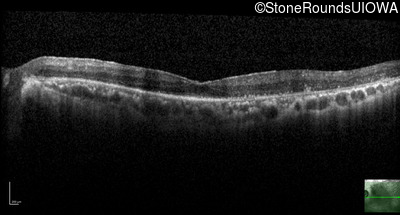

AR Retinitis Pigmentosa (IA1aiii)

Age at visit: 62 years

OD OS

This 62 year old man had poor night vision as a teenager and developed difficulty with his peripheral vision in his early forties. His parents both grew up in the small village in Taiwan.

Diagnosis & molecular findings

Disease Gene Allele 1 variant(s) Allele 2 variant(s) Inheritance mode

AR Retinitis Pigmentosa EYS Cys2139Tyr TGT>TAT Cys2139Tyr TGT>TAT AR